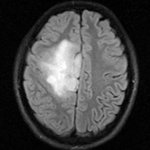

this is the fixed T2 reference image. All images are aligned into this space this is the fixed T2 reference image. All images are aligned into this space lleft this is the DTI Baseline scan, to be registered with the T2 this is the DTI tensor image, in the same orientation as the DTI Baseline

fixed image/target

FLAIR